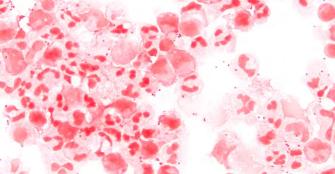

MENINGOCOCCAL-DISEASE